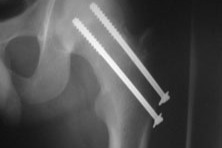

Despite the smile, the situation is a bit complicated! My brother suffered a motorcycle accident and had to operate the femur, he put two screws on it. Although the operation was paid for by the government, my brother will need about six months to recover completely and in the first three, he will not be able to walk, and to be alone at home. We are from Brazil and my brother lives alone in Porto, in Portugal, and so we brought my mother from Brazil to take care of him for the first few months, but we need help with emergency travel expenses and more medication! My mother is retired and I'm finishing my studies at the moment, so we can't afford all the costs!

Apesar do sorriso, a situação é um pouco complicada! Meu irmão sofreu um acidente de moto e teve de operar o fêmur, colocou dois parafusos. Embora a operação tenha sido paga pelo governo, meu irmão vai precisar de uns seis meses para se recuperar completamente e nos primeiros três, não poderá ficar sozinho. Meu irmão mora no Porto em Portugal e estamos então enviando minha mãe do Brasil para cuidar dele nos primeiros meses, mas precisamos de ajuda para as despesas de viagem em urgência e mais medicamentos! Minha mãe está aposentada e eu estou terminando meus estudos no momento, logo não temos dinheiro para arcar com todos os custos!